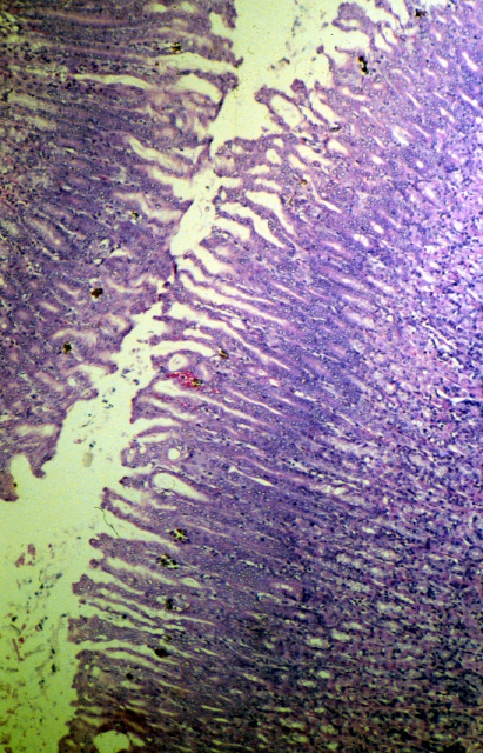

Forty rats, in groups of ten, were orally dosed with corn oil, corn oil and 2,000 mg/kg trichloroethylene (TCE), corn oil and 2,000 mg/kg lead carbonate, or a mixture of 2,000 mg/kg each TCE and lead carbonate, in an effort to determine whether or not dual administration of both TCE and lead would have an additive effect on neurotoxicity and overall health as indicated by behavioral and physiologic measurements and tissue pathology. A functional observational test battery (FOB) was performed before, during, and after dose administration to assess dose-related changes. The FOB testing assessed behavioral and physiologic measurements such as gait, open field activity, posture, grip strength, and handling reactivity. Pathological examination included assessing dosing related changes in the testis, spleen, heart, liver, kidney-adrenals, and brain.

Results indicated that each compound was toxic individually, and that the combination of the two neurotoxicants provided conflicting indications of both reduced and additive toxicity. The toxicity of lead carbonate caused the vast majority of toxic consequences in the study. A reduction in body weight and an increased resistance to cage removal were the only statistically significant changes observed in the FOB that were due to concurrent administration of lead and TCE. Organ-to-body weight and organ-to-brain weight calculations showed evidence of a statistical difference between the lead and lead/TCE dosed animals for liver, kidney-adrenals, and body weight. The significance of these changes is not fully understood.